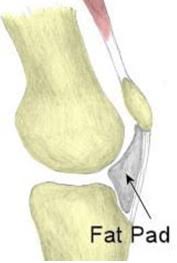

Patellar Fat Pad Abnormalities Radsource